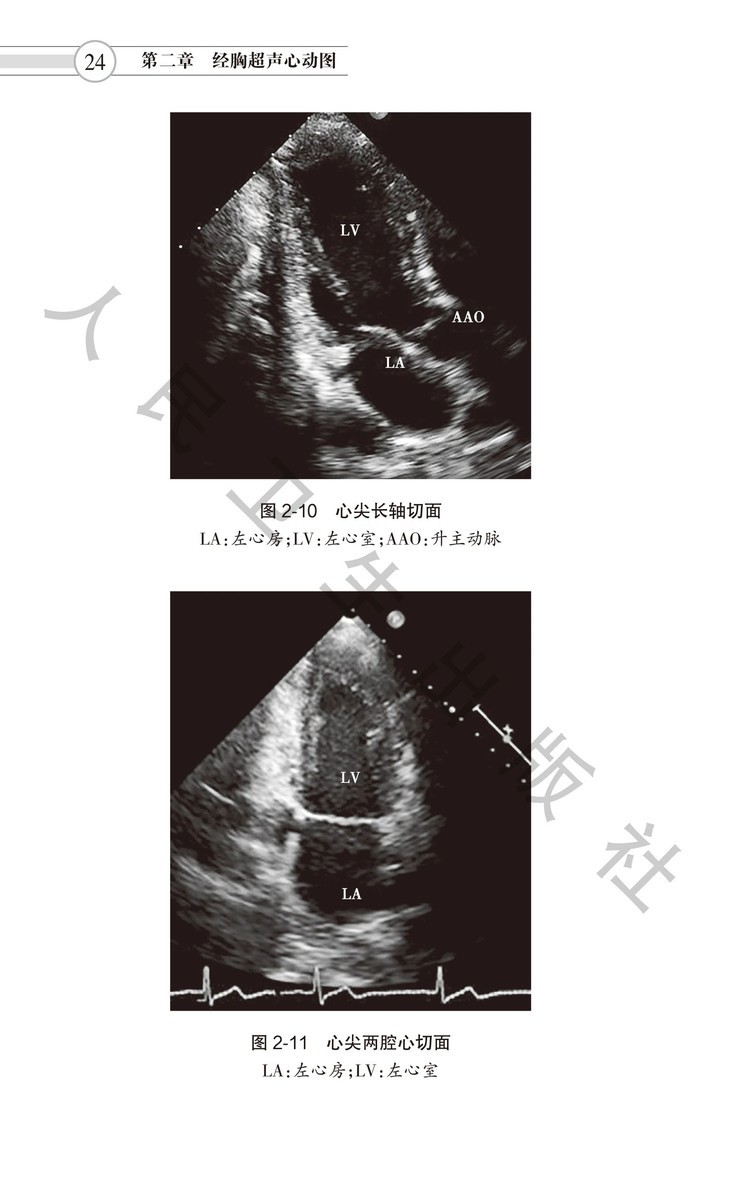

本书是中国医师协会超声医师分会组织编写,邀请众多国内一流心脏超声专家参与、研究和讨论,在2016年出版的《超声心动图检查指南》基础上修订而成。本指南分为七章。涵盖经胸超声、经食管超声、右心造影、负荷超声、床旁超声心动图等各类技术,尤其是超声心动图在各种常见心血管疾病诊断中的应用。涉及超声心动图检查适应证、禁忌证、 检查要点、注意事项和超声报告结论须涵盖内容等,旨在规范超声医师检查行为,适合各年资医师学习阅读,是指导超声医师临床工作的规范性用书。